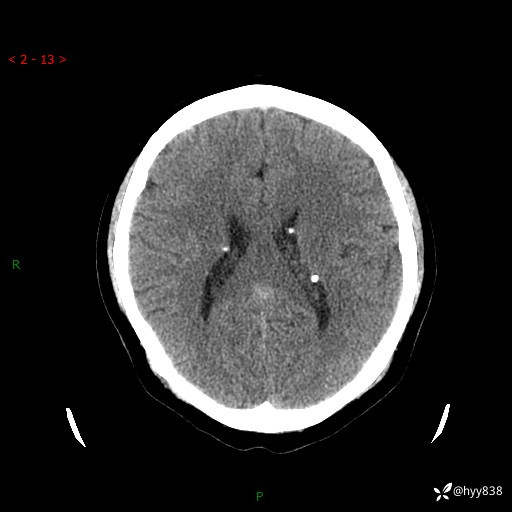

病例年轻小伙,早早的就切除了右侧肾脏,他怎么了---结果公布~

患者性别:男

患者年龄:28岁

简要病史:右肾肿瘤术后,常规复查

辅助检查:CT

临床诊断:右肾肿瘤术后

腹部CT+颅脑CT平扫